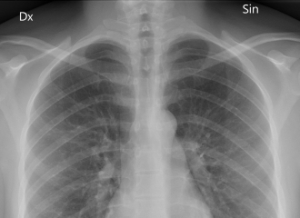

胸部X光片(图片来源:wikipedia)